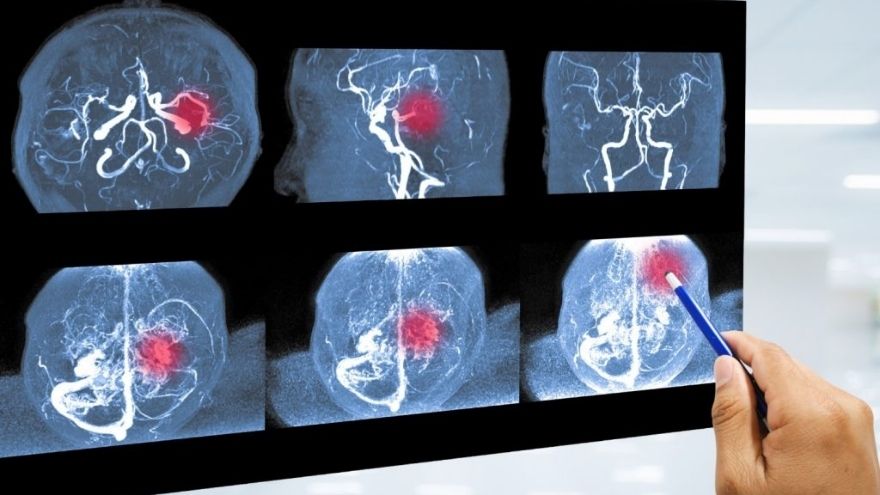

Beyin anevrizmasının teşhisi, genellikle görüntüleme teknikleri sayesinde yapılır.

Bilgisayarlı tomografi (BT): Kanama varlığını tespit eder.

Manyetik rezonans görüntüleme (MR): Anevrizmanın yerini ve büyüklüğünü belirler.

BT anjiyografi ya da MR anjiyografi: Damar yapısını detaylı gösterir.